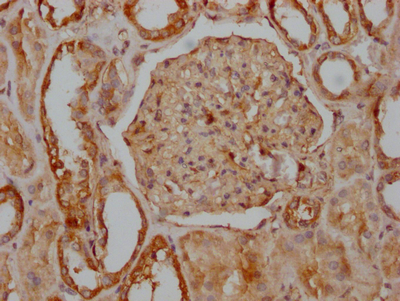

• IHC image of CSB-RA548303A0HU diluted at 1:100 and staining in paraffin-embedded human kidney tissue performed on a Leica BondTM system. After dewaxing and hydration, antigen retrieval was mediated by high pressure in a citrate buffer (pH 6.0). Section was blocked with 10% normal goat serum 30min at RT. Then primary antibody (1% BSA) was incubated at 4℃ overnight. The primary is detected by a Goat anti-rabbit IgG polymer labeled by HRP and visualized using 0.05% DAB.